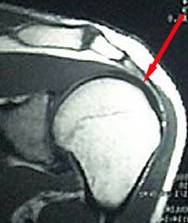

Sehnenriss - Schulter. Typisch sind starke Bewegungseinschränkungen und Versteifungen. Die MRT-Untersuchung auch Kernspintomografie genannt ist ein bildgebendes Verfahren.

In der Folge kann der Schultermuskel seine Funktion vollständig einbüßen. Häufig treten die Schmerzen nachts in Seitenlage auf. Untersuchungen und Diagnose Ultraschall Sonographie. Sehnenriss in der Schulter richtig behandeln Vier Muskeln halten Schultergelenk. Die MRT-Untersuchung auch Kernspintomografie genannt ist ein bildgebendes Verfahren. Typisch sind starke Bewegungseinschränkungen und Versteifungen. Als nahezu fast ausschließlich muskulär geführtes Gelenk ist die Schulter auf intakte Sehnen angewiesen. Bei altersbedingten Abnutzungserscheinungen können kleine Schäden der Muskeln über Monate bis Jahre bestehen ohne dass Betroffene Schmerzen haben. About Press Copyright Contact us Creators Advertise Developers Terms Privacy Policy Safety How YouTube works Test new features Press Copyright Contact us Creators.